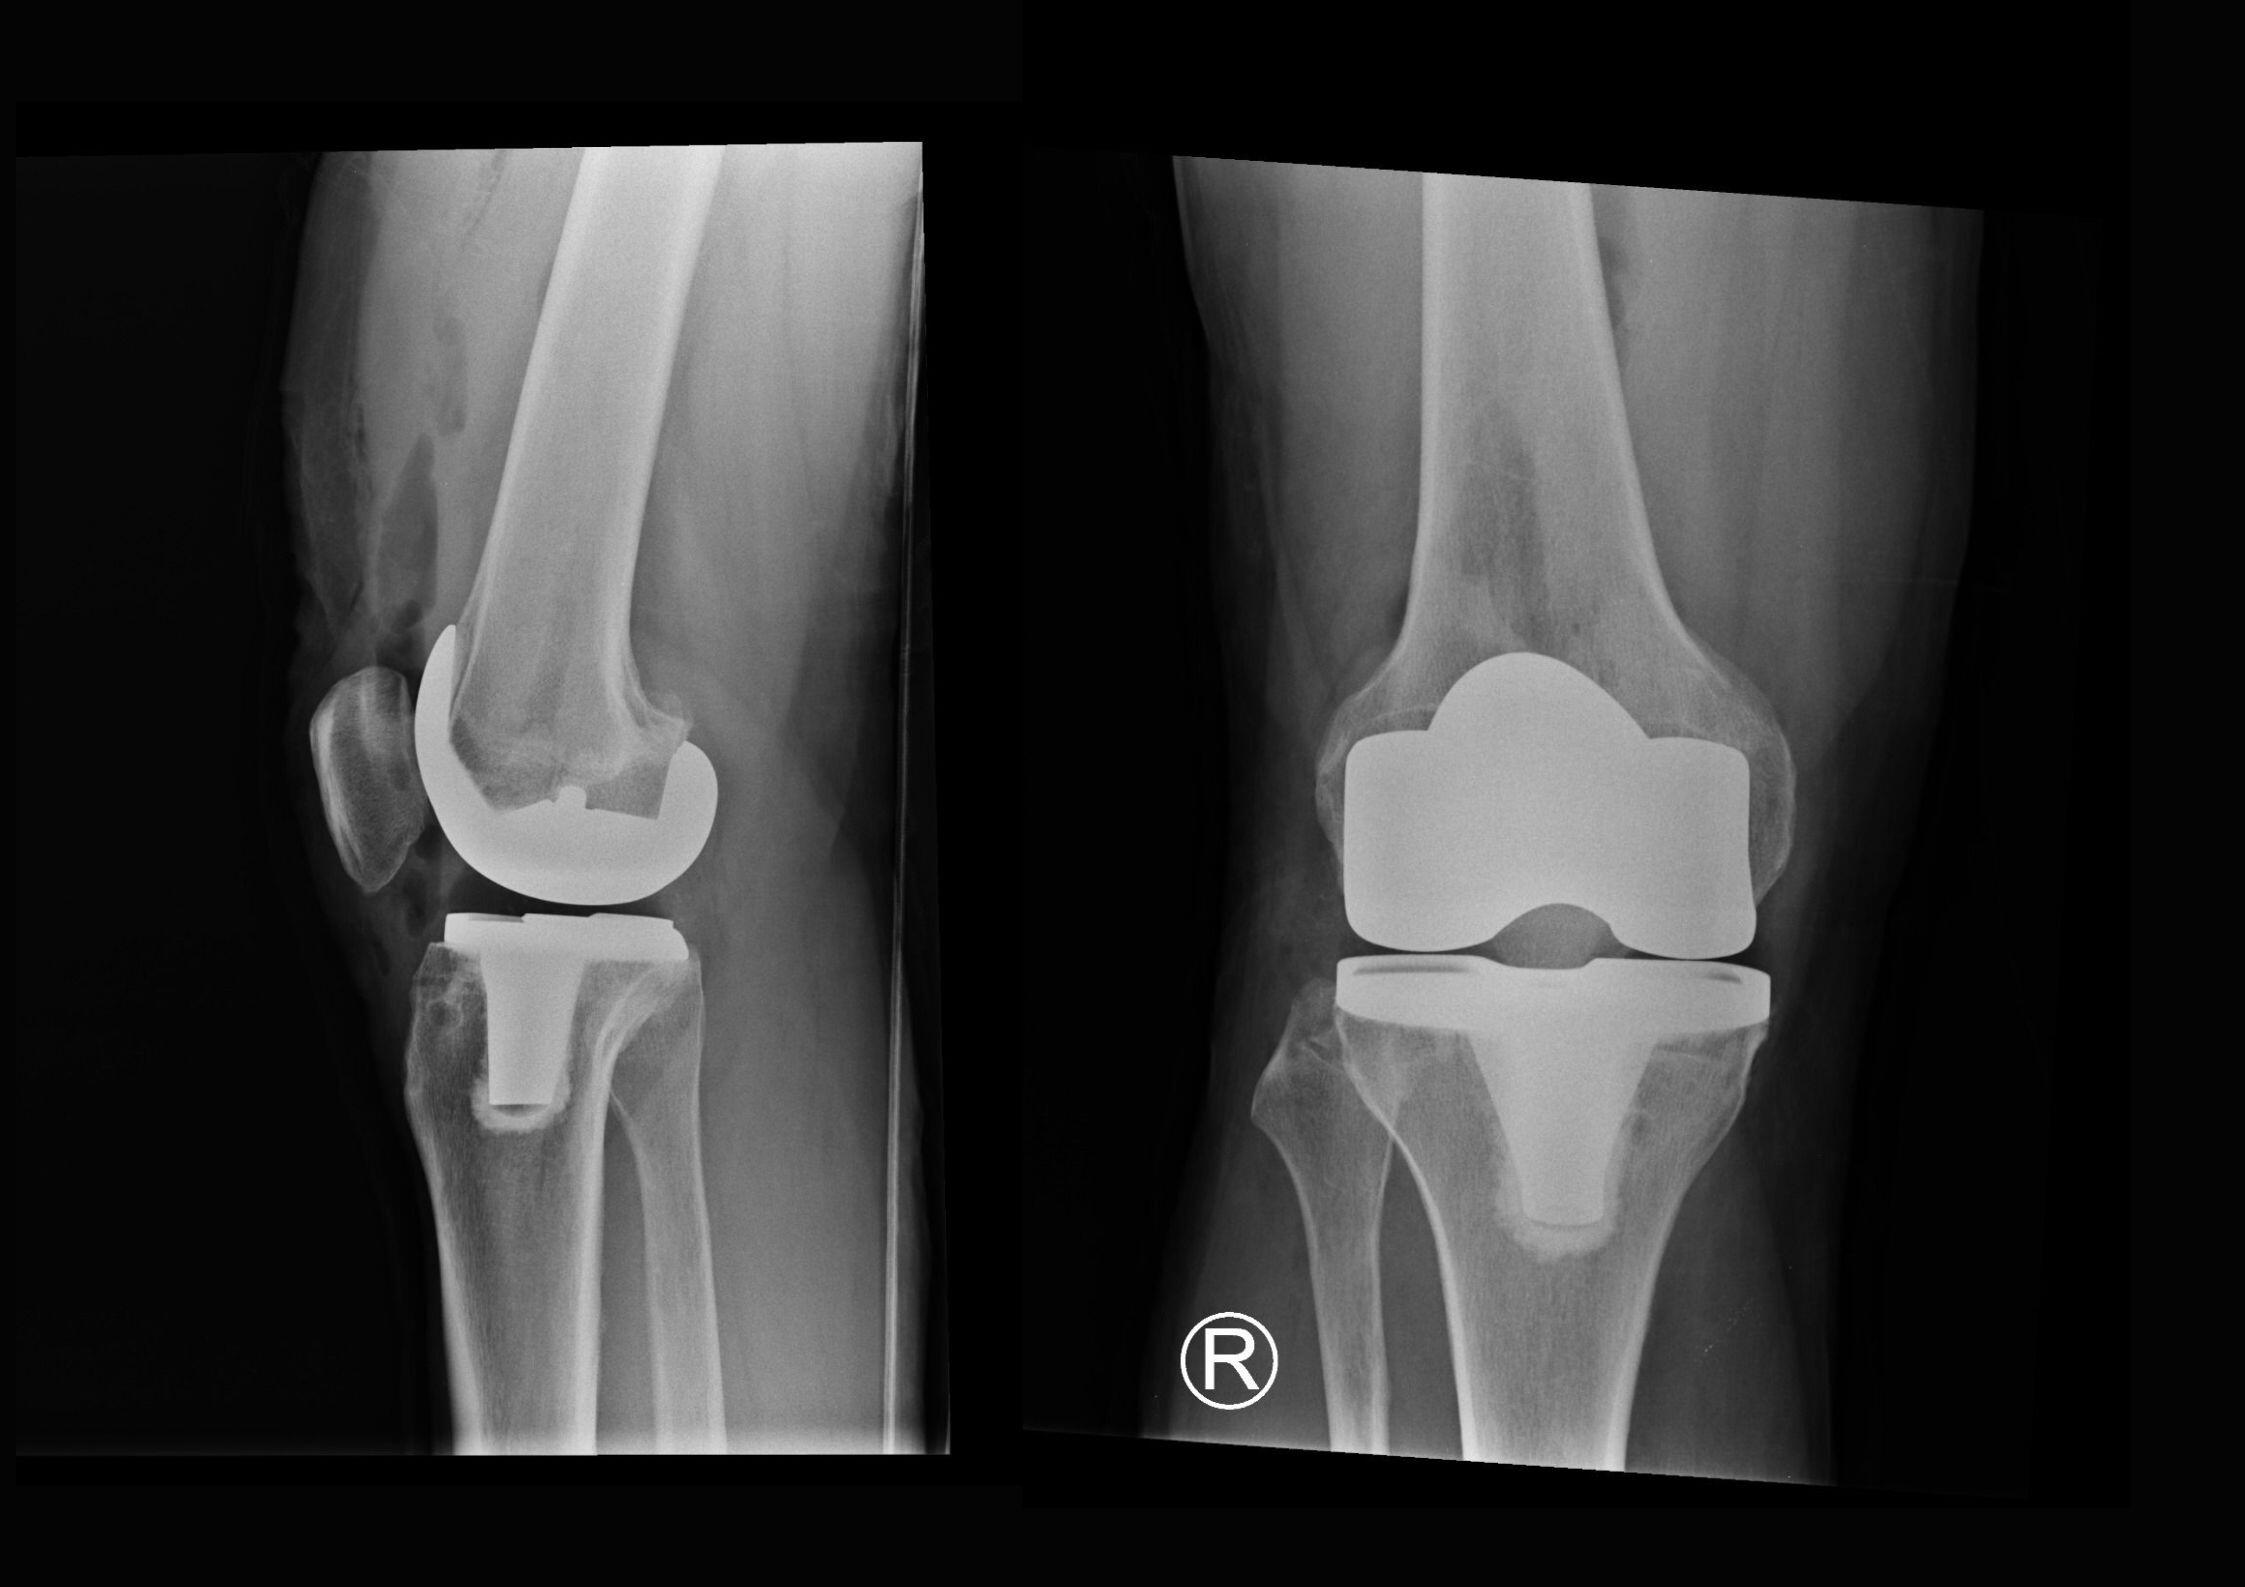

Setelah ketemu dr Theri, dan diskusi, diputuskan operasi 12 Desember. Theri juga sudah memilih merek dan tipe implant pada lutut saya nanti. Buatan Amerika. Saya tidak khawatir kalau usia implant itu hanya 25 tahun. Saya percaya, kelak akan ada teknologi yang lebih maju lagi!

Lutut kanan baru dengan implan dari Amerika.

Jadi memang sudah harus diganti. Kata Theri, implant saya size-nya paling besar. Karena tulang lutut saya besar. "Seharusnya sudah perfect", tegasnya.